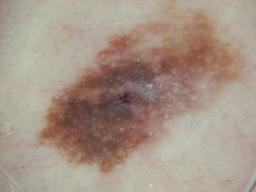

{

"age_approx": 80,

"anatom_site_general": "upper extremity",

"clin_size_long_diam_mm": "4.00",

"concomitant_biopsy": true,

"diagnosis_1": "Benign",

"diagnosis_2": "Benign melanocytic proliferations",

"diagnosis_3": "Nevus",

"diagnosis_4": "Nevus, Atypical, Dysplastic, or Clark",

"diagnosis_confirm_type": "histopathology",

"family_hx_mm": true,

"image_type": "dermoscopic",

"melanocytic": true,

"personal_hx_mm": true,

"sex": "male"